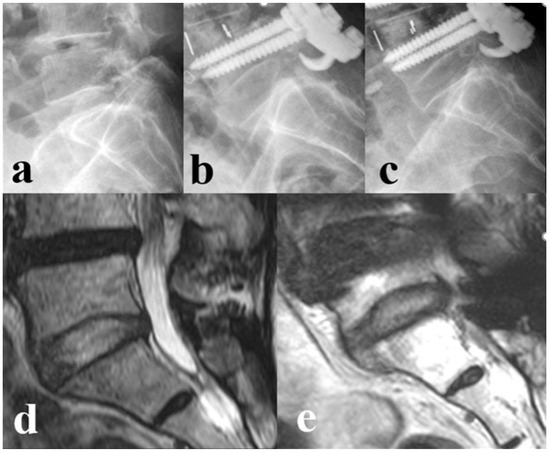

Indications for Additional Pedicle Subtraction Osteotomy in Iatrogenic Flatback After Short-Segment Fusion Surgery

by Sung-Min Kim, In-Seok Son, Yong-Chan Kim, Xiongjie Li and Maolin Jin

Medicina 2025, 61(9), 1624; https://doi.org/10.3390/medicina61091624 - 8 Sep 2025

Background and Objectives: This study aimed to identify radiographic predictors and optimal cut-off values for determining the need for additional pedicle subtraction osteotomy (PSO) in patients with iatrogenic flatback syndrome following short-segment (≤3 levels) fusion surgery. Materials and Methods: From 2011 [...] Read more.

Background and Objectives: This study aimed to identify radiographic predictors and optimal cut-off values for determining the need for additional pedicle subtraction osteotomy (PSO) in patients with iatrogenic flatback syndrome following short-segment (≤3 levels) fusion surgery. Materials and Methods: From 2011 to 2022, a total of 49 patients who underwent deformity correction for iatrogenic flatback following short-segment fusion at a single institution were included. We divided all patients into group A (n = 33, only anterior column realignment, ACR) and group B (n = 16, ACR combined with PSO). Among group A patients, we further divided them into two subgroups: The Excessive group, who developed excessive anterior disc height distraction (EADH) during surgery, and the Non-excessive group, who did not. The Receiver Operating Characteristic (ROC) curve was used to determine the cut-off values for spinopelvic parameters associated with the decision to perform additional PSO. Results: Group A had a significantly lower number of previously fused segments compared to Group B (p < 0.001). Preoperative C7 sagittal vertical axis (C7SVA, p = 0.026) and its correction (p = 0.003) in group B were greater than those in group A. Group B showed a significantly more kyphotic preoperative fused segment angle (FSA) compared to Group A (p = 0.001). Postoperatively, EADH occurred in 7 patients (21.2%) in Group A, while no cases were observed in Group B. Subgroup analysis revealed that the dynamic segment angle (DA) was significantly lower in the Excessive group compared to the Non-excessive group (p < 0.001). The optimal cut-off values of preoperative radiographic parameters for selecting PSO were: C7-SVA > 242.8 mm, FSA > −3.2°, and DA < 4.3°. Conclusions: ACR alone and ACR combined with PSO showed satisfactory outcomes in patients with iatrogenic flat back. For selected patients with preoperative C7SVA > 242.8 mm, FSA > −3.2°, or DA < 4.3°, additional PSO may be reasonable to help optimize sagittal alignment. Full article

Show Figures

Figure 1